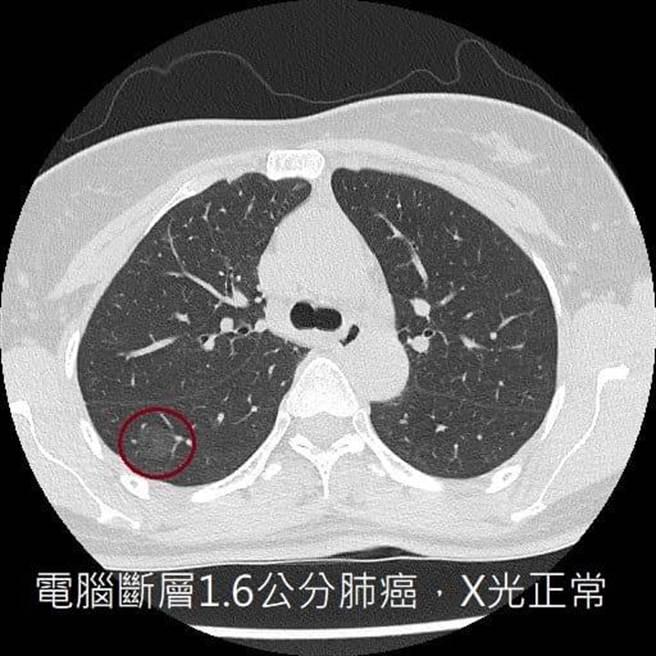

「千万不要以为X光正常就等于没有肺癌」,医师苏一峰脸书分享,一名中年妇女不抽菸、常煮菜,在无症状的情况下,安排电脑断层,一照竟发现「1.6公分的肺癌」。

苏一峰指出,对于早期肺癌患者来说,胸部X光已不是一个够敏感的检查工具,因为它只能找到大于1、2公分的病灶,且病灶还不能躲在骨头、心臟大血管或横膈等器官的死角位置,被挡住就看不见了。

他呼吁大家,不要以为胸部X光正常等于没有肺癌,除了维持良好生活习惯,一旦身体不适,最好安排更仔细的检查,及早发现、及早治疗。